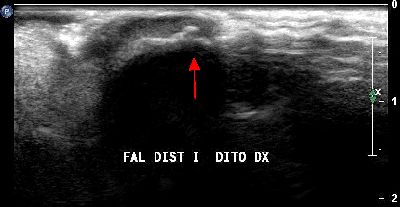

Microavulsione falange distale primo dito (img. 02) microavulsione falange distale primo dito 02